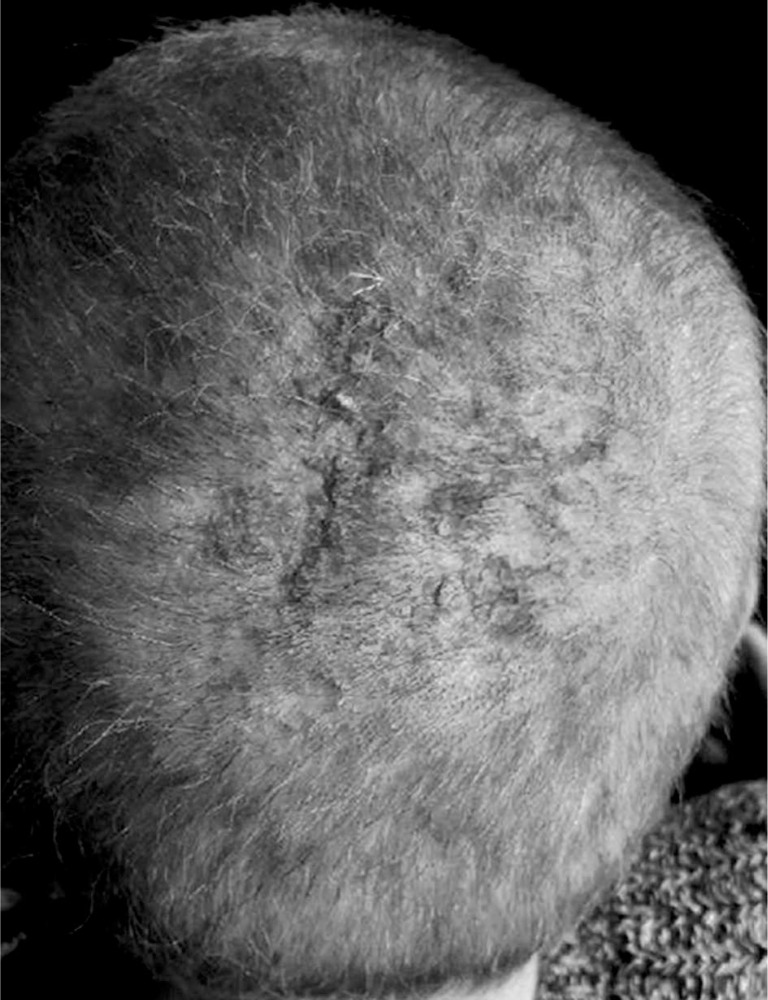

A 47-year-old woman with a history of hypothyroidism and supraventricular tachycardia who was besides in good health reported to the Dermatologic Outpatient Clinic due to a focal hair loss in the occipital area of the scalp. The lesion was 5 cm large, of irregular shape, pearly-pink coloured, painless and non-pruritic. The skin was palpably elevated and partially covered with yellowish scale (Figure 1). The patient firstly noticed small hair loss a couple months before the admission and it gradually became larger. She had no history of previous dermal diseases.

Figure 1.

The asymptomatic, alopecic lesions on the scalp with central yellowish plaque scale